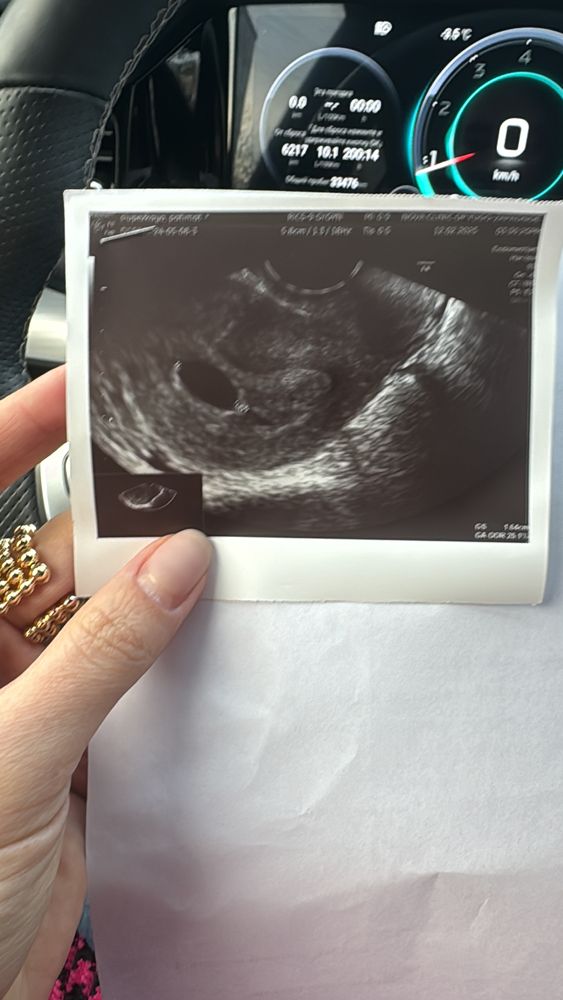

Плодное яйцо 16,4 мм но желтое тело сегодня не увидели .

Фатима, 1. Желточный мешочек. 2. Сто процентов анэмбриония, при диаметре ПЯ более 10мм, он отчётливо виден на любом аппарате УЗИ, даже на древнем.

У Вас скорее всего желточный мешочек отсутствует, на таком сроке и при таком размере плодного яйца он уже, конечно, должен быть.

Девочки всем привет! Хгч 14300 на сегодняшний день, говорят это не показатель 😭